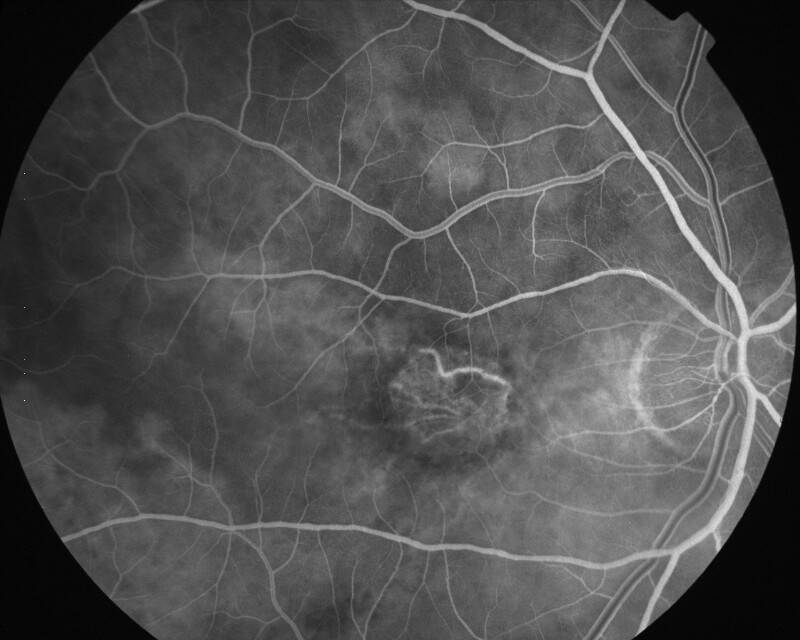

ATROPHIE AREOLAIRE CENTRALE

IMG0002.JPG